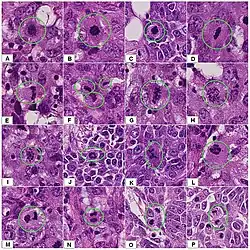

Diagnostic marker

In histopathology, the mitosis rate (mitotic count or mitotic index) is an important parameter in various types of tissue samples, for diagnosis as well as to further specify the aggressiveness of tumors. For example, there is routinely a quantification of mitotic count in breast cancer classification.[74] The mitoses must be counted in an area of the highest mitotic activity. Visually identifying these areas, is difficult in tumors with very high mitotic activity.[75] Also, the detection of atypical forms of mitosis can be used both as a diagnostic and prognostic marker. For example, lag-type mitosis (non-attached condensed chromatin in the area of the mitotic figure) indicates high risk human papillomavirus infection-related cervical cancer. In order to improve the reproducibility and accuracy of the mitotic count, automated image analysis using deep learning-based algorithms have been proposed.[76] However, further research is needed before those algorithms can be used to routine diagnostics.

-

Normal and atypical forms of mitosis in cancer cells. A, normal mitosis; B, chromatin bridge; C, multipolar mitosis; D, ring mitosis; E, dispersed mitosis; F, asymmetrical mitosis; G, lag-type mitosis; and H, micronuclei. H&E stain.

Normal and atypical forms of mitosis in cancer cells. A, normal mitosis; B, chromatin bridge; C, multipolar mitosis; D, ring mitosis; E, dispersed mitosis; F, asymmetrical mitosis; G, lag-type mitosis; and H, micronuclei. H&E stain.